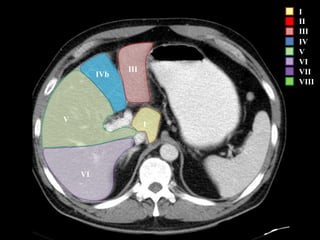

IVb III

I

II

III

IV

V

VI

VII

VIII

IVb

I – Entre cava y porta

II – el más superior de los izquierdos

III – Por debajo del II

IV – por delante de la vesícula

V – por detrás de la vesícula

VI – relación con riñón derecho

VII – el más posterior de los segmentos superiores

VIII – domo hepático

Las claves de la segm. Hepática